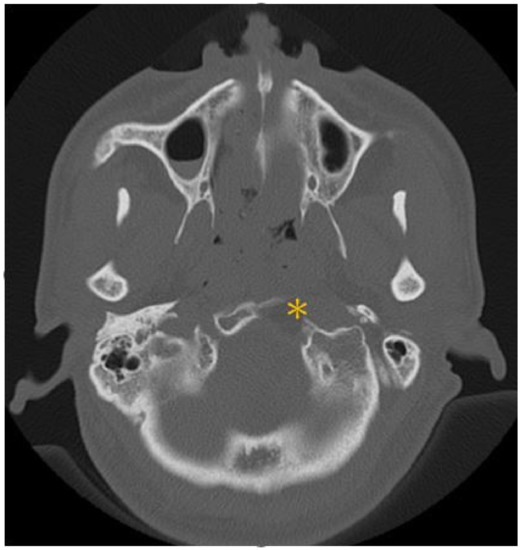

| Present case | Huang et al. | 48M | Dysphagia, hoarseness, tongue atrophy | JF, Clivus, HC, CA | IX, X, XII | T1 iso T2 hypo | + | nil | Endoscopic decompression surgery + prednisolone (10 mg/day for 100 days, oral) | 3 y |